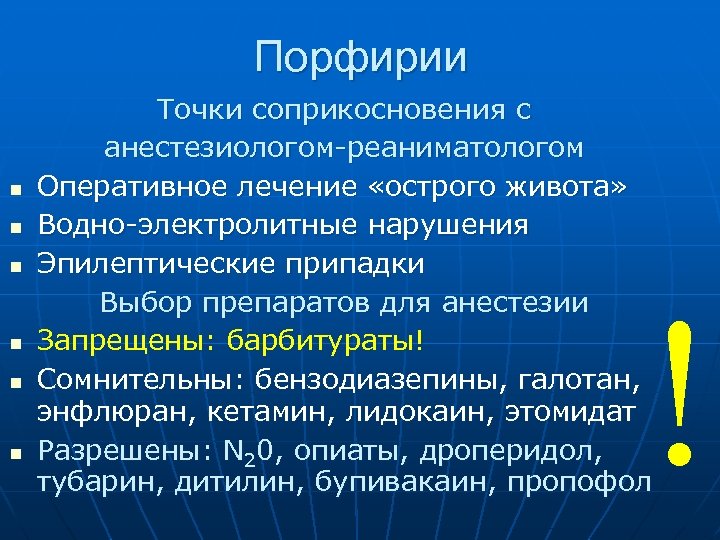

Порфирии n n n Точки соприкосновения с анестезиологом-реаниматологом Оперативное лечение «острого живота» Водно-электролитные нарушения Эпилептические припадки Выбор препаратов для анестезии Запрещены: барбитураты! Сомнительны: бензодиазепины, галотан, энфлюран, кетамин, лидокаин, этомидат Разрешены: N 20, опиаты, дроперидол, тубарин, дитилин, бупивакаин, пропофол !